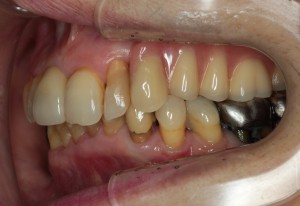

症例⑤

上左右の奥歯を失ってしまったため、保険の入れ歯を入れたが、違和感が強く、しっかり噛むことができないため、インプラントを併用した入れ歯を作ることで違和感なく、しっかり噛むことができるようになった。 また通常の入れ歯は、はずれないようにするため金属のバネを歯に引っ掛けるため見た目も悪いが、インプラントによって固定されているためバネもなく、見た目も非常に良いものとなっている。

術前

術前レントゲン写真

術後レントゲン写真